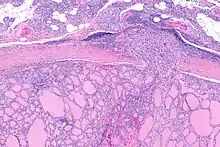

| Micrograph of follicular thyroid carcinoma showing a location where the cancer grows through the fibrous capsule. H&E stain. | |

It is impossible to distinguish between follicular adenoma and carcinoma on cytological grounds. If fine needle aspiration cytology (FNAC) suggests follicular neoplasm, thyroid lobectomy should be performed to establish the histopathological diagnosis. Features sine qua non for the diagnosis of follicular carcinoma are capsular invasion and vascular invasion by tumor cells. Still, focuses of the capsular invasion should be carefully evaluated and discriminated from the capsular rupture due to FNA penetration resulting in WHAFFT (worrisome histologic alterations following FNA of thyroid).